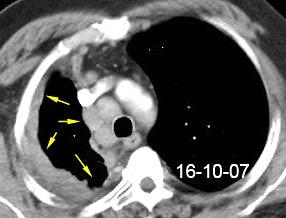

40. EMPIEMA PLEURAL. ORIGEN HEPÁTICO